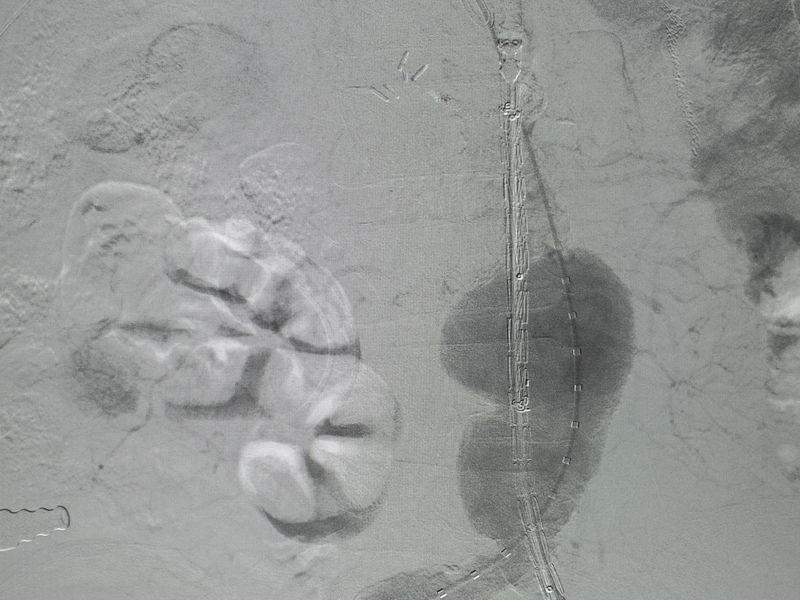

Anevrizmalar tanı konduktan sonra bulundukları bölgeye göre değerlendirilirler. Belirli çapın üzerinde ve patlamış olanlar derhal ameliyat edilmelidir. Damar çapı müdahale sınırının altında olanlar belirli aralıklarla takip edilmelidirler. Bu dönemde ek risk faktörleri kesinlikle ekarte edilmelidir. Hipertansiyon kontrol altına alınmalı hasta kendini travma ve ani darbelerden korumalıdır. Sigara kesinlikle bırakılmalıdır. Sigara içimi anevrizmalı takip edilen hastalarda rüptür (patlama) riskini artırmaktadır. Tedavi açık yöntemlerle yapılacağı gibi (Resim 1) EVAR dediğimiz Angio laboratuvarında kateter aracılığı ile anevrizmaya stent yerleştirme şeklinde de yapılabilmektedir. (Resim 2) Bu yöntemle kasık bölgesinden ilerletilen bir klavuz tel ile damara stent yerleştirilerek hasta aynı gün ayağa kalkabilmektedir. Elbette hangi yöntemin kullanılacağı hastaya göre karar verilmektedir.